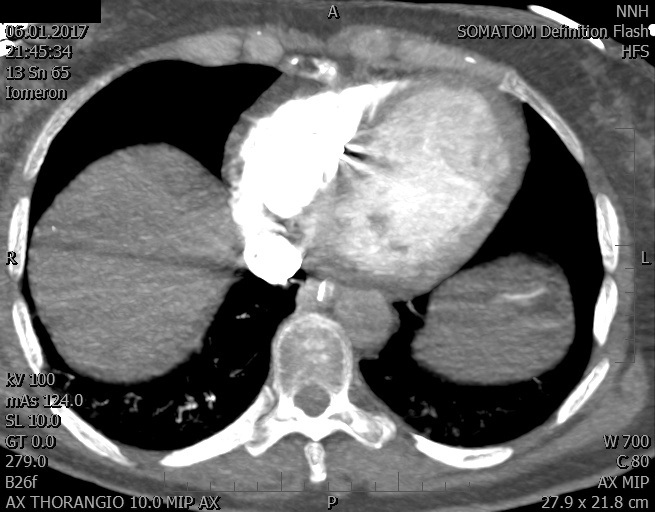

Video 1 - Akutní koronarografie prokázala normální nález na věnčitých tepnách s výjimkou suspekce na lehký spasmus na pravé koronární tepně.Echokardiograficky byla zjištěna těžká dysfunkce dilatované levé komory s nezvětšenou pravou komorou (video 2).

Video 2 - Echokardiograficky byla zjištěna těžká dysfunkce dilatační levé komory s nezvětšenou pravou komorou.Pro nejasnou příčinu zástavy jsme provedli i vyšetření výpočetní tomografií (CT), které vyloučilo plicní embolizaci (série 1 - soubory na konci článku). V den přijetí při přetrvávající oběhové nestabilitě byla nemocná opakovaně defibrilována pro fibrilaci komor se stabilizací rytmu po podání amiodaronu a mesocainu. Dle hemodynamických měření se jednalo o těžký kombinovaný šok. Vstupní laboratorní vyšetření bylo bez větších pozoruhodností. Posléze jsme doplnili anamnézu od příbuzných a zjistili, že pacientka užila do dvou hodin před srdeční zástavou první tabletu amoxicilinu na lehký respirační infekt. Při nevýtěžnosti vstupních vyšetření a nových anamnestických informacích jsme doplnili 14 hodin po kolapsu vyšetření koncentrace tryptázy v séru, která byla extrémně zvýšena (tabulka 2), což nás vedlo k podezření na anafylaxi.